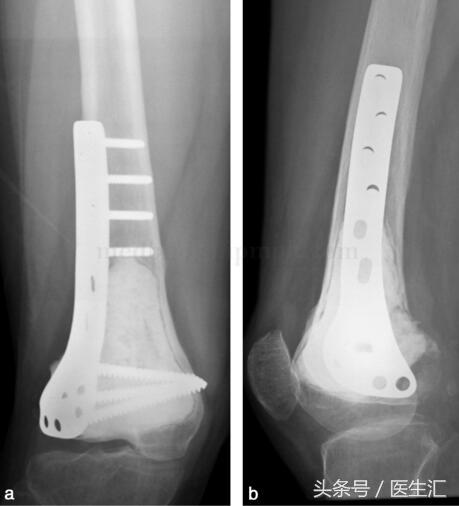

由于行軟骨下骨處植骨,故囑患者術(shù)后3個(gè)月,攝片示植骨愈合后,患肢開(kāi)始負(fù)重(圖29‐4a,圖29‐4b)。此患者已術(shù)后隨訪兩年,局部無(wú)復(fù)發(fā),胸部無(wú)轉(zhuǎn)移,植骨已愈合,功能良好。

圖29‐4

a﹒術(shù)后X 線正位片;b﹒術(shù)后X 線側(cè)位片